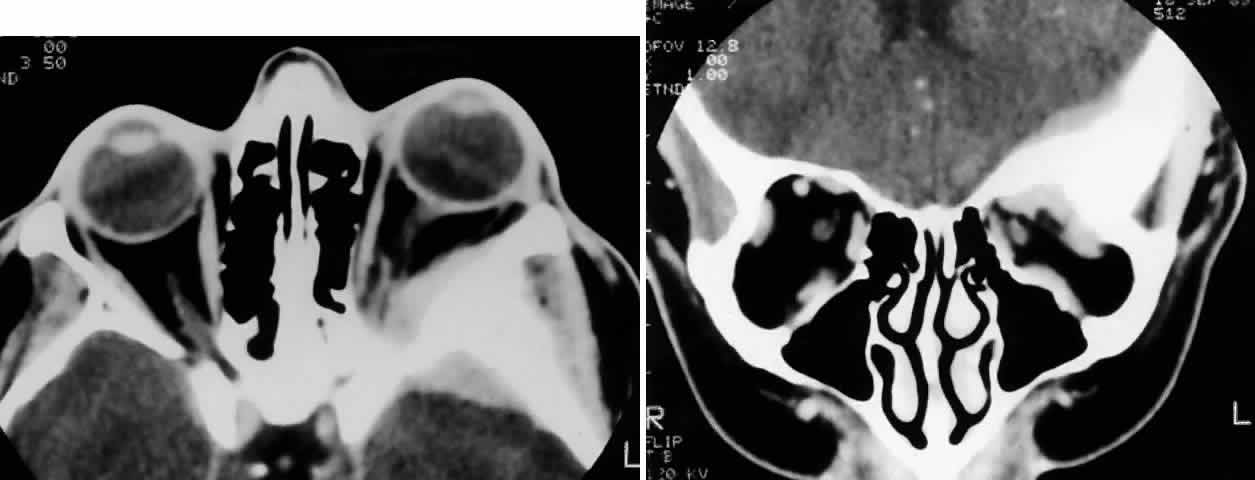

Fig. 9. A 79-year-old man had been treated for several years for chronic blepharoconjunctivitis. On examination, he had thickening of upper and lower lid margins, diffuse symblepharon, conjunctival thickening, injection, and yellowish plaque-like foci (A). Conjunctival biopsy confirmed invasive sebaceous cell carcinoma, and subtotal exenteration was performed. Tumor invasion along the globe (B) (H & E, × 32) and into muscle (C) (H & E, × 80) was noted.

Fig. 11. A 61-year-old white man noted a pigment spot in the medial canthal area of his left eye associated with intermittent subconjunctival hemorrhages lasting 6 months. On examination, there was a raised, pigmented lesion in the lower medial conjunctiva (A) measuring 20 mm across the base, with a central, pale, telangiectatic nodule 6 mm thick noted on lateral gaze (B). There was extension into the upper medial fornix and laterally in the lower fornix. There was no evidence of preauricular, submandibular, or cervical lymphadenopathy. A clinical diagnosis of conjunctival melanoma arising in primary acquired melanosis (PAM) was made. Conjunctival biopsy revealed invasive melanoma (C and D) (H & E, × 80 and × 200, respectively) arising within PAM type IB (E) (H & E, × 200). A total exenteration and split-thickness skin graft from the anterior thigh were performed, and the patient was disease-free at 6 months' follow-up.